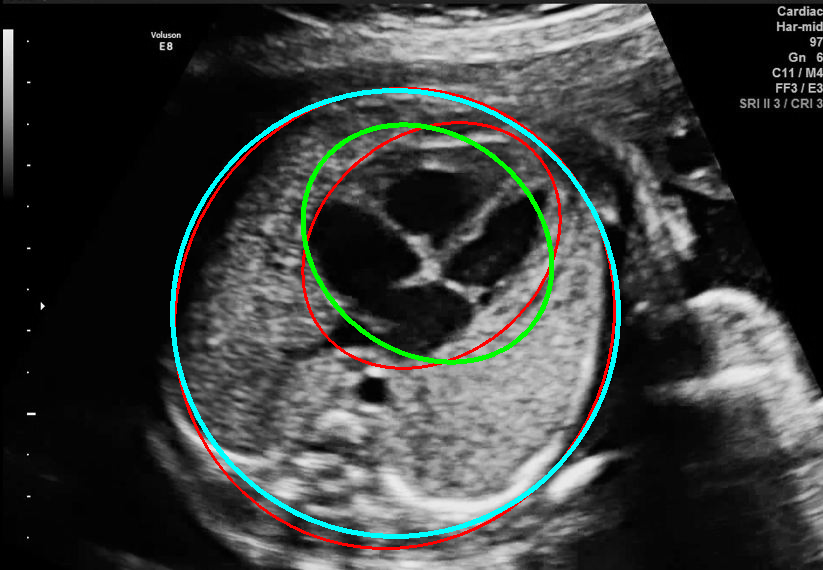

Results of ablation study.

In this section, we evaluate the effect of different loss terms in EllipseNet by ablation study. As shown in the lower part of Table. 1, IoU loss improves detection performance remarkably. EllipseNet with IoU loss achieves a gain of 0.92 and 1.16 points in cardiac and thoracic dice coefficients respectively. On the other hand, EllipseNet with only IoU loss (without ellipse regression loss defined in Eq. 5) does not achieve satisfactory performance, which demonstrate the necessarity to include the paremeters’ regression losses. It worth mentioning that the exact IoU of two rotated ellipses is always greater than that of corresponding rotated bounding boxes based on our observation. The IoU loss brings promotion in terms of bounding box IoU, which can be regarded as a lower bound of the ellipse IoU. This may explain why IoU loss is effective for ellipse regression in another view.

As shown in Fig. 3 , both the proposed ellipse regression loss and IoU loss are necessary for ellipse detection. If the EllipseNet only supervised by IoU loss (first column), the model fails to optimize the major and minor axis separately, and the predicted ellipses degenerate into circles like the CircleNet. It is clear that the supervision of IoU loss can help to improve the prediction of location and shape (first and second row) and to correct the angle (last row).